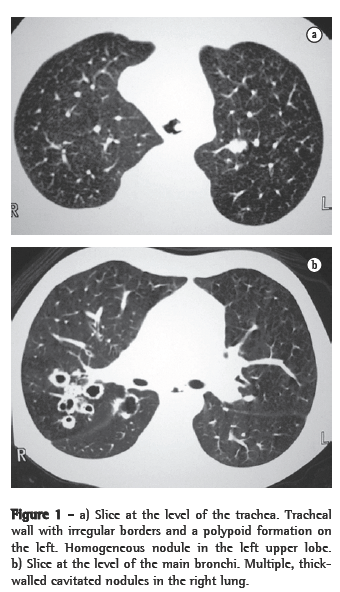

In all eight cases, the CT scans revealed polypoid formations in the trachea. In one case, injury to one of the main bronchi was identified. Seven patients presented involvement of the pulmonary parenchyma. In all eight cases, there were cavitated polypoid lesions, with irregular internal borders and walls of various thicknesses, multilobulated in six cases and presenting confluence of the lesions in five (Figures 1 through 5). Solid nodules were seen in six patients. An air-fluid level was observed in only one patient. The lesions were predominantly in the lung bases in three patients and in the middle thirds in two, whereas they were evenly distributed in two. In one patient, the lesions were accompanied by a mass, and, in another patient, they were accompanied by consolidation. In the latter case (Figure 5), there was malignant degeneration in multiple lesions. Signs of air trapping were also observed in one case. There were no identified instances of lymph node enlargement or pleural effusion.

Chest X-rays can occasionally produce findings suggestive of the disease, such as the combination of solid or cavitated pulmonary nodules and vegetative nodular lesions in the trachea or in the main bronchi. Unlike the pulmonary nodules, which are often identified on simple chest X-rays, intralumen papillomas in the trachea or bronchi are rarely visible on X-rays.(4) In practice, therefore, the disease is rarely diagnosed on the basis of chest X-ray findings. The nodules are typically multiple, well defined, of various dimensions, cavitated and thick-walled, being more numerous in the basal and posterior lung regions.(3,4) The cavitated nodules can be air-filled or, when infected, can present an air-fluid level.(4)

Chest X-rays are inferior to CT scans of the chest, especially those performed using spiral CT (volumetric acquisition), in the initial phases of pulmonary dissemination, due to the fact that CT better characterizes and allows better visualization of nodular tracheobronchial vegetation, Tomographic findings include focal or diffuse airway narrowing caused by the nodules. The nodules form on the mucosal surface, and their invasion into the lumen is best evaluated using CT.(3) These alterations are easily correlated with the disease when there is a clinical history of papillomatosis.(4) Other findings related to airway obstruction and accompanying infections are atelectasis, consolidations, air trapping and bronchiectasis.(2-4) In our sample, polypoid formations in the trachea were observed on all of the CT scans Seven patients presented involvement of the pulmonary parenchyma, characterized by cavitated polypoid lesions with irregular internal borders and walls of various thicknesses, with a multilobulated aspect and a tendency toward confluence. Solid nodules were seen in six patients. None of the patients presented lymph node enlargement or pleural effusion.